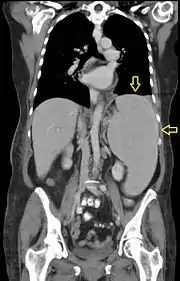

Syndrome tumoral

Le syndrome tumoral est lié à la dissémination des blastes hors de la moelle osseuses et de la accumulation dans les organes. Il peut se traduire cliniquement par[31] :

- une augmentation de volume de certains organes : splénomégalie, hépatomégalie ;

Lorsque la masse tumorale (c'est-à-dire le nombre de blastes) est très importante, un syndrome de lyse tumorale peut se déclencher. Il est lié à la destruction des blastes qu'elle soit spontanée ou liée à un traitement. Le contenu intracellulaire est alors relargué dans le sang ce qui entraîne des perturbations des concentrations sanguines en ions (potassium, phosphate), visibles sur le ionogramme. Cela peut entraîner une hyperkaliémie, délétère pour le rythme cardiaque ou une élévation de l'acide urique (hyperuricémie) pouvant conduire à des atteintes rénales via la formation de cristaux d'urate. La prise en charge du syndrome de lyse vise à rétablir un ionogramme normal par hydratation et administration d'électrolytes ; l'hyperuricémie peut être traitée par rasburicase, une enzyme qui dégrade l'acide urique.

Le syndrome de leucostase est observé en cas d'infiltration massive des organes par les cellules leucémiques. Il se manifeste par une forte concentration des blastes dans le sang (blastose), une fièvre et des symptômes respiratoires et ou neurologiques. Ce syndrome est une urgence thérapeutique dont l'issue peut être fatale par détresse respiratoire.